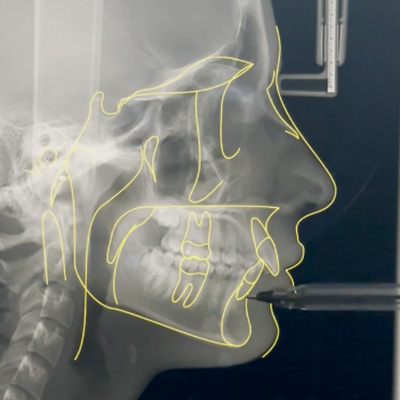

Profundice en la técnica del Hilo Invisible BOT con clases teóricas y casos reales — un procedimiento que ofrece estética, comodidad y resultados al paciente.

SALA DE PROCEDIMIENTOS

Siga clases prácticas y la evolución de casos clínicos reales directamente desde la clínica del Dr. Ary Nunes.